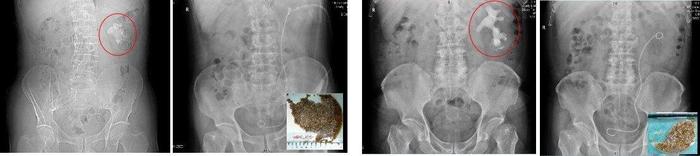

图3:鹿角形肾结石术前术后比照